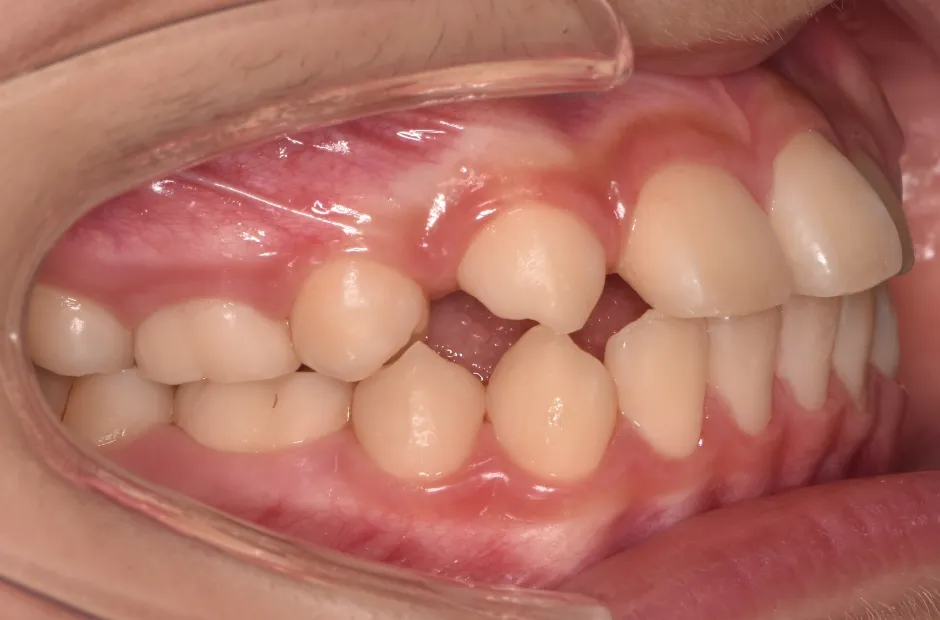

治療症例

ブラケット矯正

前歯部反対咬合

| 診断名・主訴 | 前歯部反対咬合 |

|---|---|

| 年齢・性別 | 14歳・男性 |

| 治療期間・回数 | 1年2か月 |

| 治療に用いた主な装置 | ブラケット矯正 |

| 抜歯部位 | なし |

| 治療費 | 60万円(税抜) |

| リスク・副作用 | 装置による違和感・疼痛・歯肉退縮・歯根吸収・虫歯のリスクなど |

治療前

治療後